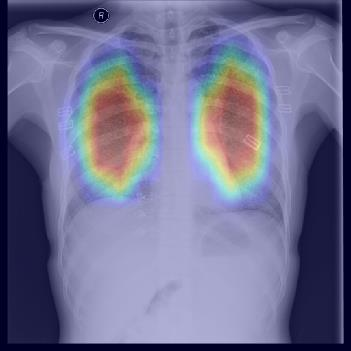

Chest X-ray (CXR) is the most typical diagnostic X-ray examination for screening various thoracic diseases. Automatically localizing lesions from CXR is promising for alleviating radiologists' reading burden. However, CXR datasets are often with massive image-level annotations and scarce lesion-level annotations, and more often, without annotations. Thus far, unifying different supervision granularities to develop thoracic disease detection algorithms has not been comprehensively addressed. In this paper, we present OXnet, the first deep omni-supervised thoracic disease detection network to our best knowledge that uses as much available supervision as possible for CXR diagnosis. We first introduce supervised learning via a one-stage detection model. Then, we inject a global classification head to the detection model and propose dual attention alignment to guide the global gradient to the local detection branch, which enables learning lesion detection from image-level annotations. We also impose intra-class compactness and inter-class separability with global prototype alignment to further enhance the global information learning. Moreover, we leverage a soft focal loss to distill the soft pseudo-labels of unlabeled data generated by a teacher model. Extensive experiments on a large-scale chest X-ray dataset show the proposed OXnet outperforms competitive methods with significant margins. Further, we investigate omni-supervision under various annotation granularities and corroborate OXnet is a promising choice to mitigate the plight of annotation shortage for medical image diagnosis.